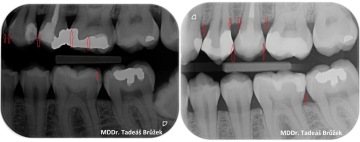

Nahrazení původní nepřesné amalgámové výplně fotokompozitní výplní. Z rentrenového snímku před a po je vidět, že se nejedná pouze o estetickou záležitost. Fotokompozitní výplň umožňuje přesnější ošetření a snižuje pravděpodobnost vzniku dalších zubních kazů u spojení zubu a staré nepřesné výplně.